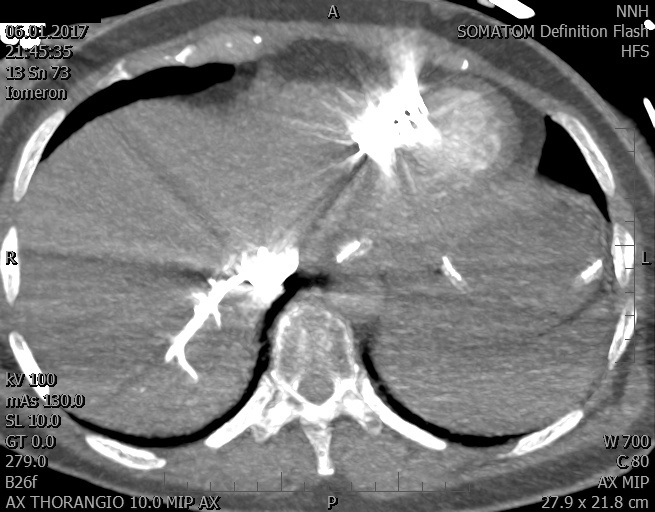

Video 2 - Echokardiograficky byla zjištěna těžká dysfunkce dilatační levé komory s nezvětšenou pravou komorou.Pro nejasnou příčinu zástavy jsme provedli i vyšetření výpočetní tomografií (CT), které vyloučilo plicní embolizaci (série 1 - soubory na konci článku). V den přijetí při přetrvávající oběhové nestabilitě byla nemocná opakovaně defibrilována pro fibrilaci komor se stabilizací rytmu po podání amiodaronu a mesocainu. Dle hemodynamických měření se jednalo o těžký kombinovaný šok. Vstupní laboratorní vyšetření bylo bez větších pozoruhodností. Posléze jsme doplnili anamnézu od příbuzných a zjistili, že pacientka užila do dvou hodin před srdeční zástavou první tabletu amoxicilinu na lehký respirační infekt. Při nevýtěžnosti vstupních vyšetření a nových anamnestických informacích jsme doplnili 14 hodin po kolapsu vyšetření koncentrace tryptázy v séru, která byla extrémně zvýšena (tabulka 2), což nás vedlo k podezření na anafylaxi.